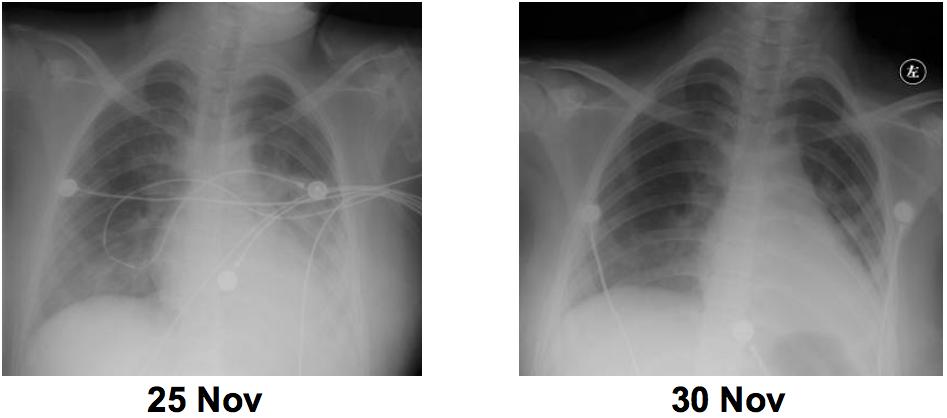

NIV 治疗危重症新冠肺炎(病例5)

病例5是一个典型病例。38岁,女,咳嗽,3月26日发烧,4月1日证实有PCR 因严重呼吸困难和高流量氧气治疗,于4月4日转移至GIRH ICU。入ICU时的评估:RR:36-40bpm,呼吸窘迫,PaO2/FiO2:189mmHg。NIV:BiPAP S/T,FiO2:0.45→0.6,IPAP:14,EPAP:6。使用NIV两小时后,氧合指数升到250mmHg。但是总体来说,氧合指数会随着病情进展还会降低,此时需要上调吸入氧浓度,上调压力,才可以维持氧合指数。连续使用12天,病情好转后间歇使用。最终康复出院。